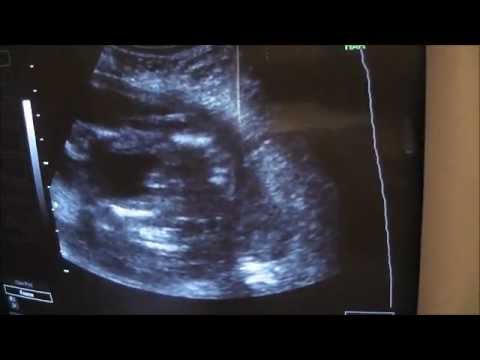

Baby Girl Ultrasound 20 Weeks 3 Days - YouTube

Baby Girl Ultrasound 20 weeks 3 days klhall494. Subscribe Subscribed Unsubscribe 2 2. 21W2D- 1st Ultrasound- Finding out the gender of our baby! - Duration: 7:16. ourlittlemushroom 157,014 views. 7:16 20 Week Ultrasound & Baby Bump Pics - Duration: 4:06. Montara Van Fleet 1,119 ... View Video